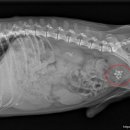

• 선부중앙동물의료센터 | 안산 고양이 이물 수술 전문 | 선부중앙동물의료센터 소화기 수술 후기 및 입원 관리

안녕하세요, 안산의 모든 반려가족분들! 선부중앙동물의료센터입니다. 🐾 고양이를 키우는 집사님들이라면 한 번쯤 '혹시 우리 아이가 이걸 먹은 건 아닐까?' 하는 걱정에 가슴이 철렁했던 적 있으실 거예요. 고양이는 호기심이 많고 혀의 돌기 때문에 이물질을 삼키기 쉬운 구조를 가지고 있거든요. 오늘은 소화기 이물...

환자들의 후기 등을 미리 살펴보는 것이 도움이 될 수 있습니다. ​ 다음으로, 병원의 시설과 장비 역시 중요한 고려 사항입니다. 최신 진단 장비(예: X-ray, 초음파, 혈액 검사 장비)를 갖추고 있는지, 수술실이나 입원실의 위생 상태는 어떠한지 등을 확인해야 합니다. 특히 응급 상황 발생 시 신속하고 정확한 진단과...

• 선부중앙동물의료센터 | 강아지 요로 결석 재발 재수술 후기

​ ​ ​ 강아지 결석 재발 재수술 후기 강아지 요로결석, 방광결석 재발로 재수술하게 된 후기 남겨봅니다. 반려견 결석은 재발률이 높은 편이라고 해서 꾸준히 관리...이번 수술은 선부중앙동물의료센터에서 진행했어요. ​ ​ ​ ​ 📍선부중앙동물의료센터 정보 주소 : 경기 안산시 단원구 선부광장1로 69 단지내상가동 2층...